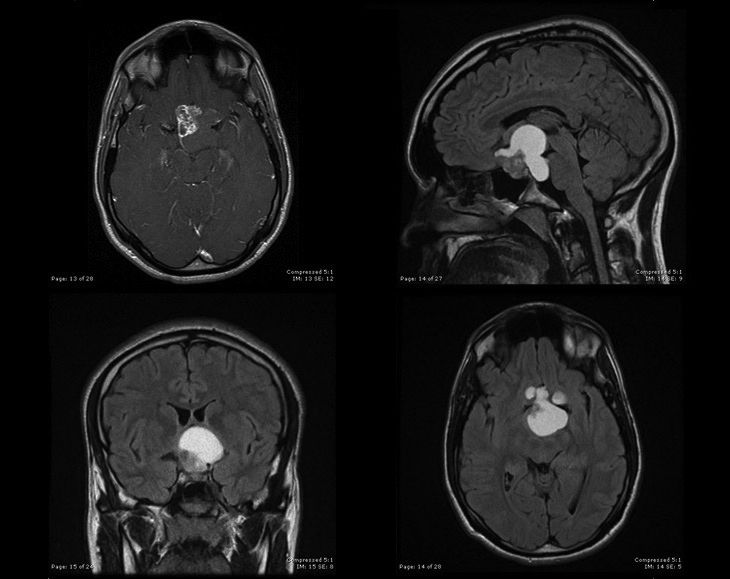

A healthy 24-year-old male presented with a history of several months of poorly localized headaches and blurred vision. Evaluation by an ophthalmologist detected the presence of bitemporal hemianopsia. MRI of the brain demonstrated a multi-lobulated mass with both cystic and solid components causing significant superior displacement of the optic chiasm. The patient subsequently underwent a subtotal resection.

The T1-weighted post-contrast image (top left), and the T2-weighted images (top right, bottom left and right) are shown here.

Based on the radiographic appearance of the mass, what is the most likely diagnosis?